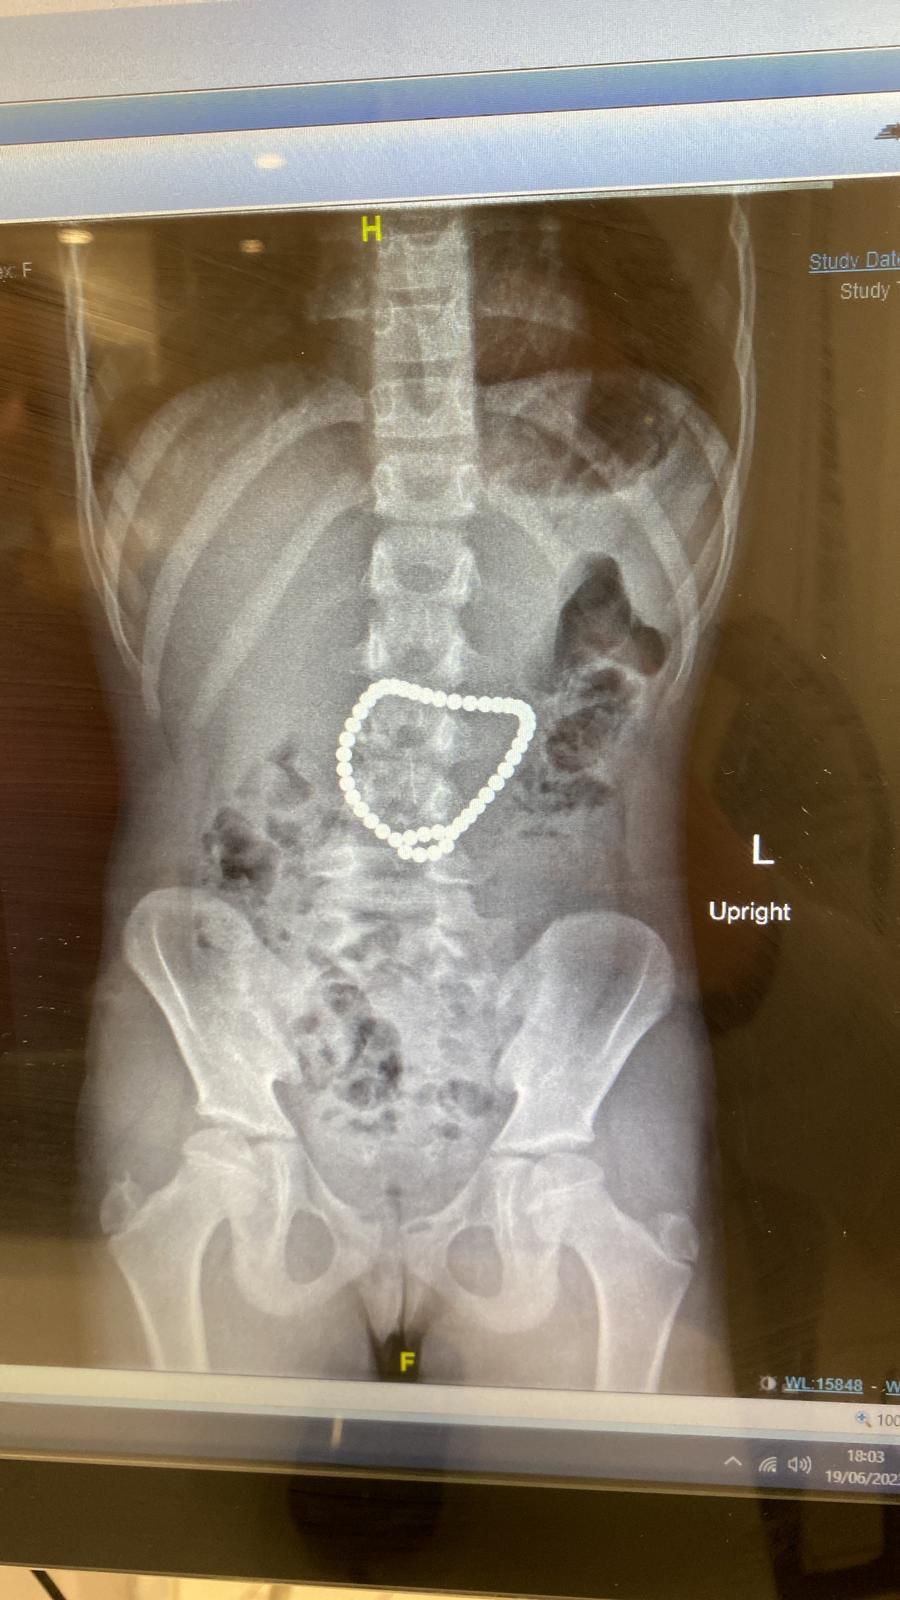

עם קבלתה במיון הילדים, חשדו הרופאים כי הילדה בלעה עצם זר, אך היא הכחישה זאת. אף על פי כן, מיהרו הרופאים לבצע צילום בטן. בצילום נמצאה שרשרת ארוכה ביותר מונחת במוצא הקיבה.

ההליך בוצע ע״י גסטרואנטרולוגית ילדים ד״ר טאף ובעזרתם של ד"ר שמאין המרדים והאחות זינה מינוביץ. במהלך הניתוח גילתה להפתעתה ד"ר טאף כי לא מדובר בשרשרת רגילה אלא באסופת מגנטים עגולים שנכרכו סביב מוצא הקיבה והמעי הדק.